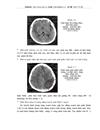

1.8.3. Chụp CLVT tưới máu não

3.2. Hình ảnh chụp cắt lớp vi tính và cộng hưởng từ